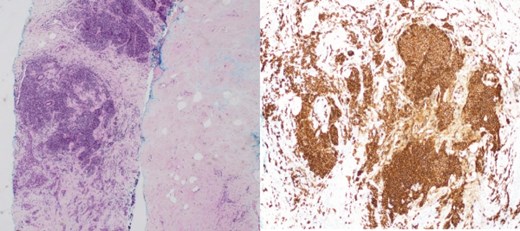

(Left) Ultrasound images of the left breast ill-defined hypoechoic mass; (Middle, Right) Ultrasound images of the axillary lymph nodes with cortical thickening and effacement of the fatty hilum.

(Left) Mammography medioloateral oblique views of bilateral breasts; (Right) Mammography cranial-caudal views of bilateral breasts: Left upper central breast shows a vague focal asymmetry corresponding to the palpable concern, and several prominent right axillary lymph nodes.

(Left) Breast core biopsy showing neoplastic lymphoproliferation around benign duct (H&E stain, 20 times magnification); (Middle) Breast core biopsy with immunohistochemical staining showing atypical lymphoid cells positive for CD20 stains; (Right) lymph node core biopsy showing distorted architecture by an infiltrate of small lymphocytes involving entire node (H&E stain, 20 times magnification).